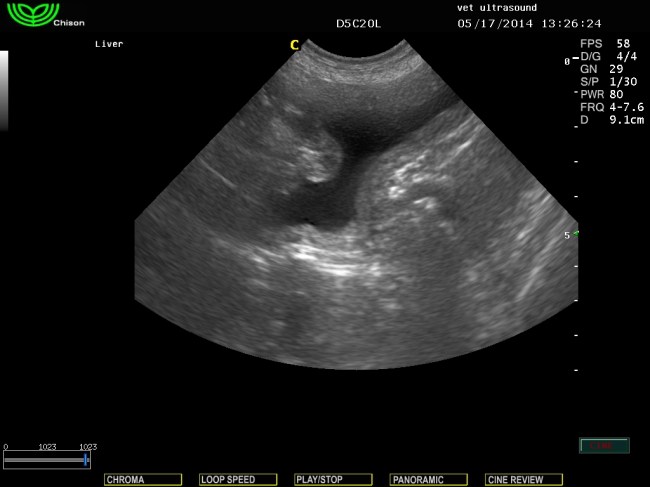

βλέπουμε το ακανόνιστο σχήμα της ουροδόχου μετά τον καθετηριασμό σε εγκάρσια τομή.